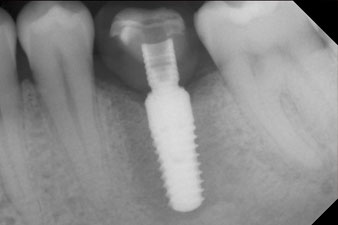

radio de contrôle

Fig. 10 : La radio de contrôle montre que l’ostéo-intégration a été réussie et que la couronne est vissée en position de manière parfaitement ajustée.